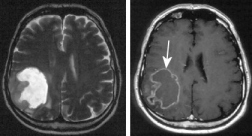

Enfermedad Alzheimer [por

mercurio de amalgama]

|

El cerebro Alzheimer perdió una grande

parte de su substancia cuando en comparación a un

cerebro sano. El mercurio esencialmente es una

parte de ese proceso.

Investigación de cerebros

de personas muertas respecto a oligoelementos

Fueron comparados dos grupos. Un grupo fueron personas que

habían muerto por la enfermedad Alzheimer, y un otro grupo

fueron todas las otras pacientes. El nivel de mercurio en

el tejido cerebral de los pacientes Alzheimer fue

aumentado, en las regiones cerebrales degeneradas por la

enfermedad Alzheimer hasta cuatro veces más (p.41).